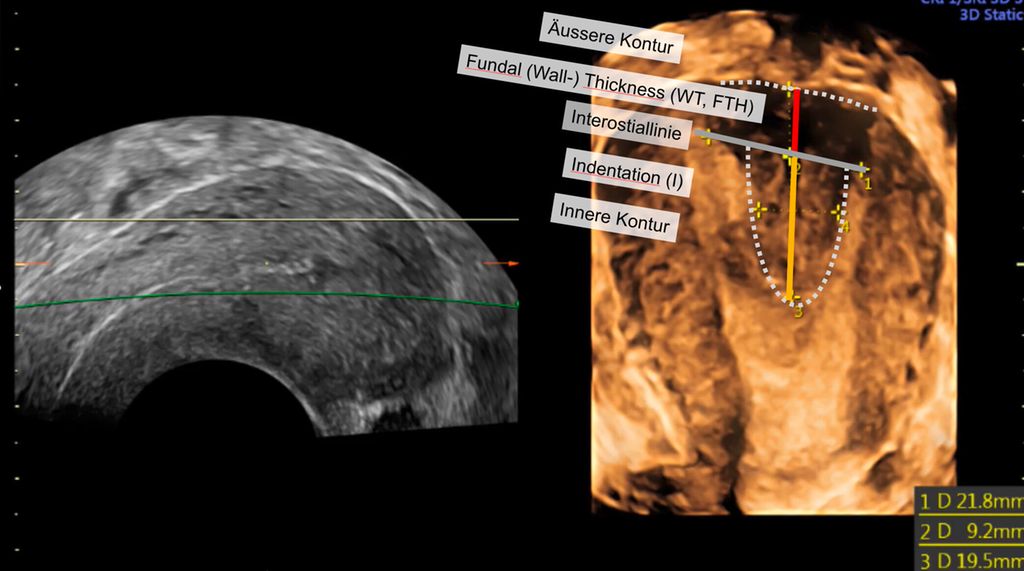

Abb. 2: Multiplanare Rekonstruktion der Koronarebene. Die äussere und innere Funduskontur sind rot eingezeichnet. Die Fundusdicke («fundal thickness», FTH) lässt sich ausmessen

Die Untersuchung wird idealerweise bei hoch aufgebautem Endometrium durchgeführt. Nach Erstellung der Koronarebene kann sowohl die äussere als auch die innere Uteruskontur dargestellt und die Fundusdicke («fundal thickness», FTH) bestimmt werden (Abb. 2). Eine allfällige Septierung ist dabei einfach erkennbar und mittels eines Messkreuzes leicht objektivierbar. Dies lässt sich einfach konstruieren: Zunächst wird eine Hilfslinie zwischen den beiden inneren Tubenostien eingezeichnet (sog. Interostiallinie). Nun kann kranial davon die Fundusdicke (bis zur Serosa) und kaudal davon die Länge des Septums sowie der Winkel der Septumspitze bzw. Carina ausgemessen werden (Abb. 3). Je nach Klassifikationssystem unterscheiden sich hier die Definitionen bzw. Massangaben, welche zur Diagnose einer Fehlbildung nötig sind. Während die ESHRE-ESGE-Guideline relativ «laxe» Kriterien vorschlägt, unter deren Anwendung viele Patientinnen die Diagnose eines Uterus (sub-)septus erhalten würden (bis zu 80%!), landen gemäss ASRM-Klassifikation viele Patientinnen in einer «Grauzone». Hier bewähren sich die CUME-Kriterien, mit deren Hilfe eine Einteilung gelingt, die am ehesten der tatsächlichen Prävalenz entspricht, und dies bei entsprechender Trennschärfe.8 Die vorgeschlagenen Kriterien zur Diagnose eines Uterusseptums sind eine Septumlänge von mindestens 10 mm, ein Winkel von <140° und ein Verhältnis Septum:Fundusdicke von >110% (Abb. 4, Tab. 1).

Abb. 3: Ausmessen der Septumlänge. Nach Anlegen der Interostiallinie (grau) zwischen den Tubenostien können die Fundusdicke und das Septum (innere Einkerbung, engl. «indentation») ausgemessen werden. Nicht eingezeichnet ist hier die Messung des Septumwinkels